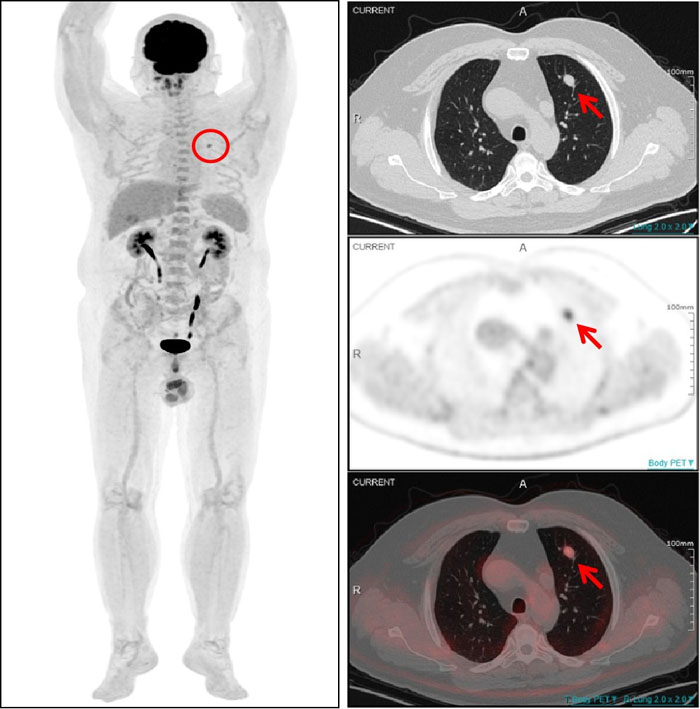

PET/CT显示:该结节伴明显异常葡萄糖高代谢(SUVmax4.5),为肺转移灶。

一名54岁男性患者曾在1年半前接受了左大腿脂肪肉瘤切除术,术后规律复查。一次常规CT检查发现其左肺上叶存在一个软组织结节,随后复查显示该结节有所增大,直径约为1.0cm。面对这一疑似转移的挑战,全景动态Total-body PET/CT 清晰显示左肺上叶结节伴明显异常葡萄糖高代谢,提示该结节为肺转移灶。基于检查结果,医生能够及时为患者制定更加个体化的治疗方案。对该患者的诊断,彰显了全景动态Total-body PET/CT 在癌症诊断领域的非凡实力。